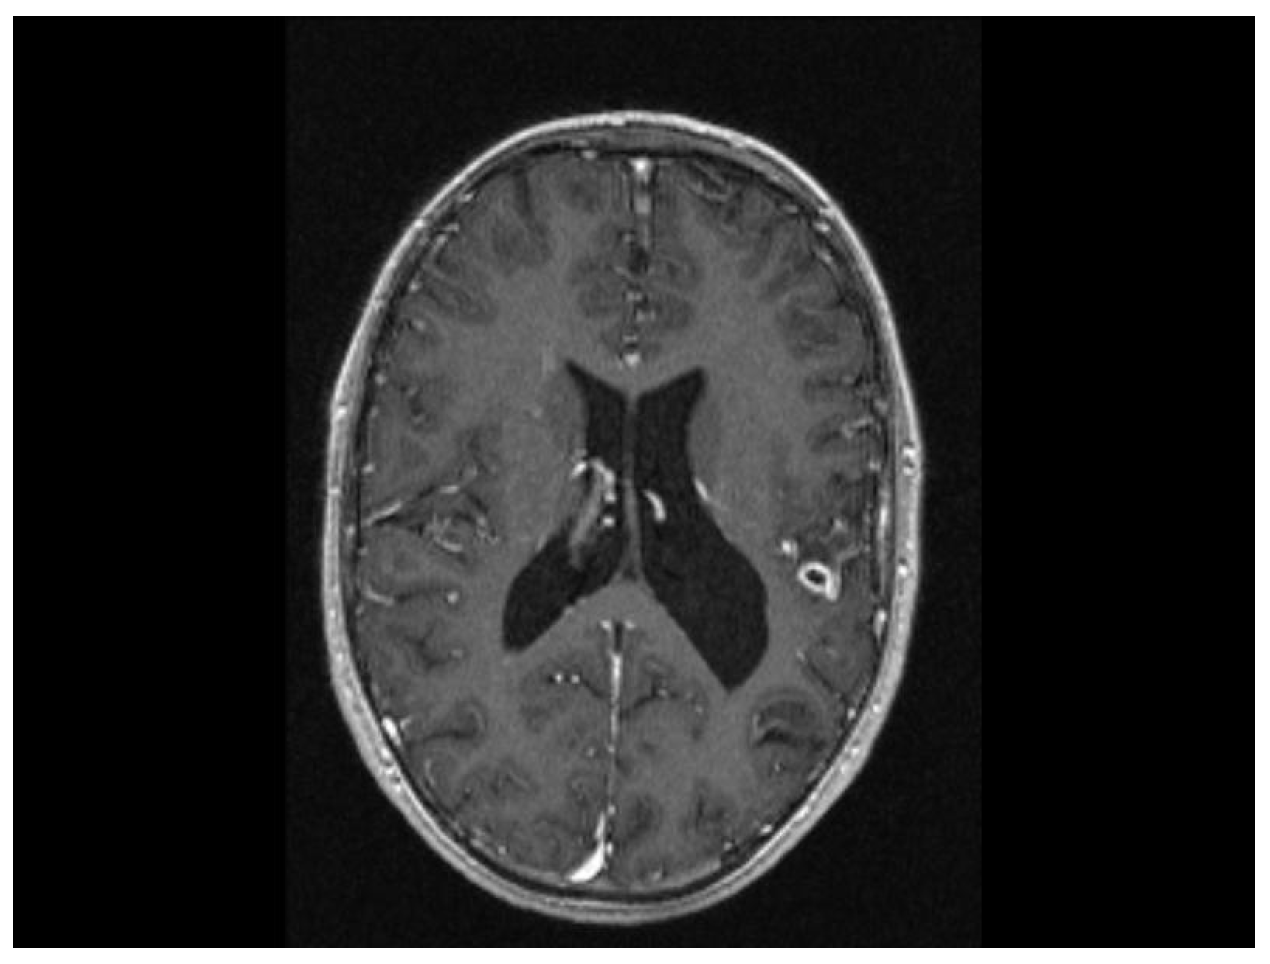

2. Case Presentation